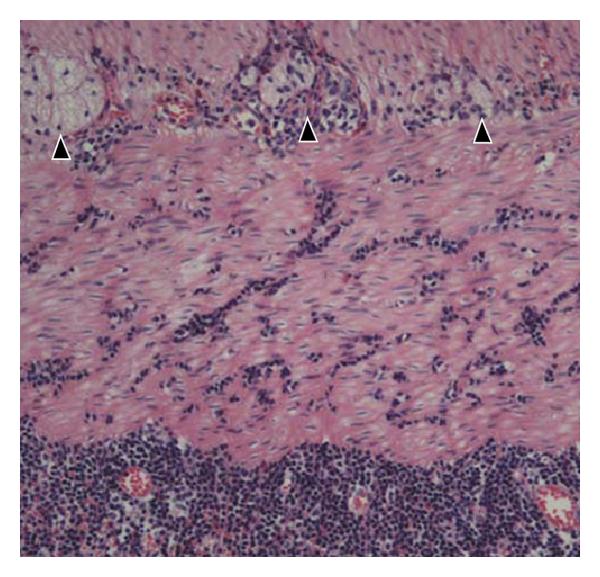

In tissue sections of the terminal ileum, lymphoid hyperplasia was only mild and the surface lining epithelium displayed only focal erosions. Intranuclear inclusion bodies indicating for adeno-virus infection were not detectable. The deeper tissue layers were strongly infiltrated by inflammatory cells including abundant CD3 positive lymphocytes. Features of inflammatory neuropathy with lymphocytes and eosinophiles in close contact to nervous cells of the plexus myentericus were found (Figure 1(e)).

The histological findings were dominated by moderate lymphoid hyperplasia and strong erythrocyte extravasates. In the deep tissue layers, infiltrating lymphocytes were only few in number. Densely packed erythrocytes were found adjacent to the nervous plexus, but morphological hallmarks of inflammatory neuropathy, demonstrated in adenovirus-positive cases 1 and 2, were not visible (Figure 1(f)).

In the present study, lymphocytic infiltration of nervous plexus, the morphological hallmark of inflammatory neuropathy, was found in two patients with adenovirus infection and intussusception (cases 1 and 2), but not in patient 3 (case 3: adenovirus negative intussusception). Our working hypothesis, that inflammatory neuropathy might be associated with injury of intestinal motility, is favoured by two recent studies by Lindberg and coworkers [13, 14]. In these studies, inflammatory neuropathy triggered by CD3 positive lymphocytes was characterized as a striking phenomenon and the underlying reason for enteric dysmotility and chronic intestinal pseudoobstruction. In this functional setting, inflammatory neuropathy could be assumed as a putative cofactor in the pathophysiological concept of adenovirus infection-associated intussusception.